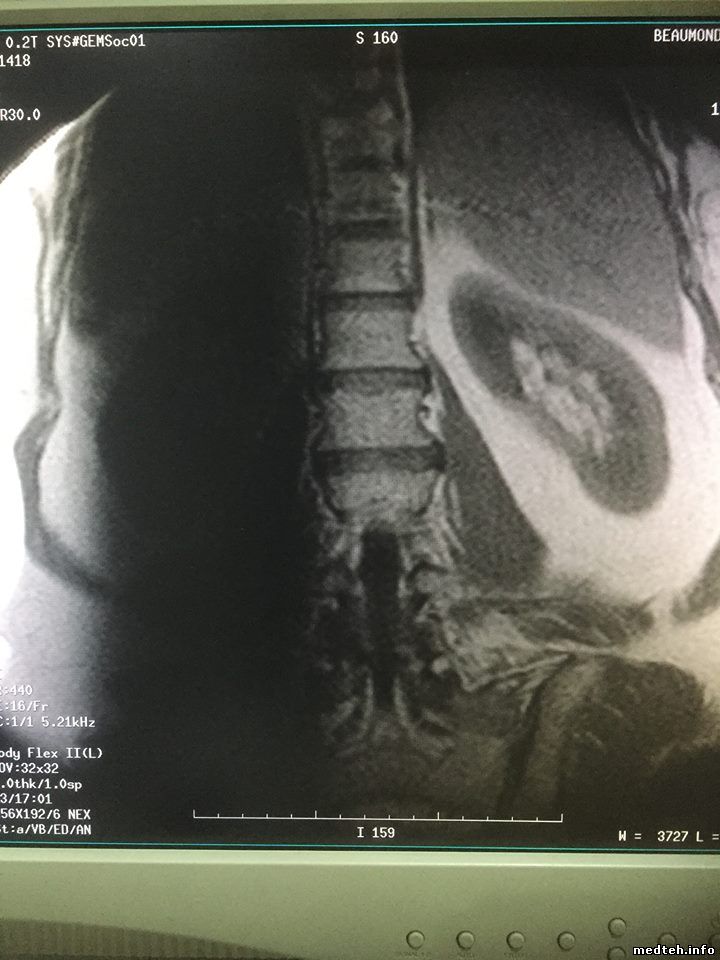

на продольном боковом срезе брюшной полости (катушка BodyFlex ) рядом с позвоночником слева вертикалный дефект картинки в виде темной полосы с размытыми краями... причина?

картинки такие:

1400157.jpg (85.3 Kb) · 5506200.jpg (95.1 Kb) · 2307948.jpg (156.9 Kb) · 2009293.jpg (158.7 Kb)

на мой взгляд, это потеря сигнала из-за наложения срезов.. смотреть чисто геометические параметры: матрицу, размер вокселя, расстояние между срезами, толщину среза.

Коллеги, закрадывается у меня мысль, что это очень напоминает сатуратор, который случайно выставили и забыли, насколько помню есть сатураторы которые не отображаются в виде сеточки, их просто в самом протоколе можно активировать и задать координаты, а тут просто как будто активировали и по умолчанию выставилась координата. Точно знаю, что на сосудах есть такие сатураторы, чтобы допустим, отсекать сигнал от вен и получать сигнал только от артерий. По маркировке, если память не изменяет по направлению фазы кодирования, ну что-то типа А или S. Попробуйте посмотреть в настройках самого протокола. Я ведь правильно понял, что это только в этой программе, такая фигня?

Мля, это какой-то добрый человек перекрутил сагиттал с сатуратором на потрохах в коронал. Не выключая сатуратор.